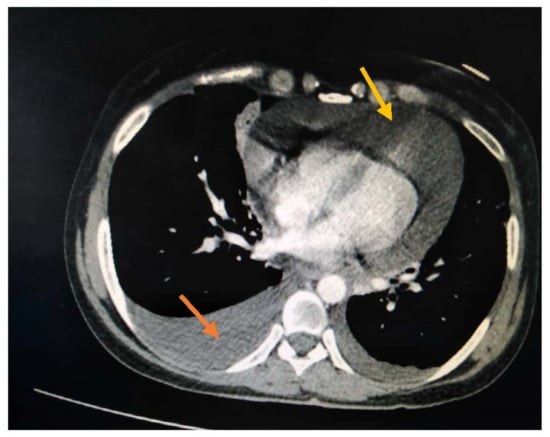

2. Case Presentation